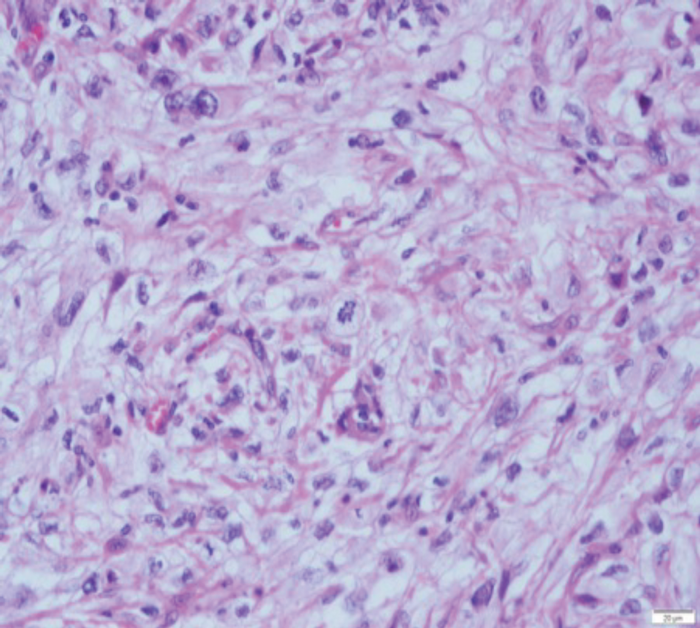

Figure 2: (A) sRCC tumour. (B) sRCC metastases to lymph node.

sRCC macroscopically, has a solid white appearance [Figure 1]. Microscopically, it contains spindle-like cells, cellular atypia and high cellularity which are features found in sarcomas [Figure 2]. They do not contain epithelial components and they can be uniform or heterogeneous. The majority will contain some carcinoma elements, while 90% will have tumour necrosis and 30% will have lymphovascular invasion. More than 80% of sRCC are found in clear cell carcinoma [10]. sRCC tends to be associated with high grade tumours however, more than 30% can also be found in low grade tumours [11]. Due to its aggressive nature and poor prognosis it is often looked at as independent prognostic factor when managing RCC.